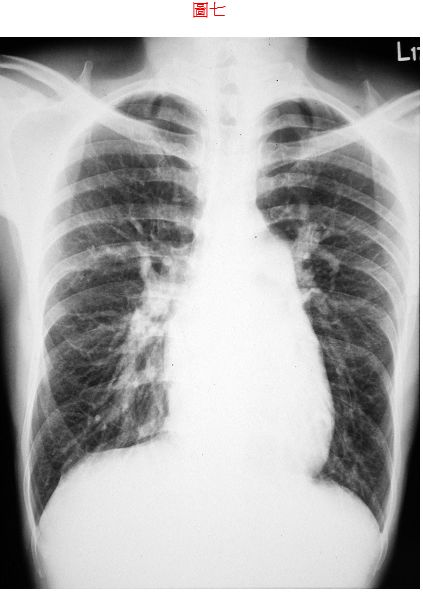

7. 病人26歲,男性,宜蘭頭城工人,主訴偶有胸悶歷經一個月,他自小開始就不適運動,胸口時有鐘擺劇動,最近常有運動相關的胸悶, 伴有心悸暈眩,有時強度運動會有發紺。既往病史未有特別。理學檢查:身高155cm、體重45.5kg、血壓108/70mmHg、心跳80/min、頸靜脈正常、PMI左5th ICS(intercostal space)的LMCL(left middle clavicular line)、RV heave、在左上胸緣有Gr. III/VI systolic ejection murmur with fixed splitting S2,未有心雜音傳移,P2加重。其他理學檢查未有不正常,胸部X光如圖7, 心電圖如圖。本病人做正確的心臟診斷是: (A) Pulmonary stenosis (B) Idiopathic pulmonary hypertension (C) Atrial septal defect (D) Aortic stenosis (E) Mitral stenosis